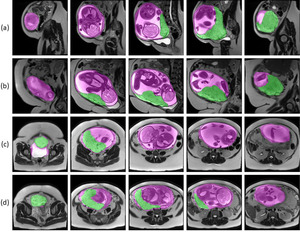

Automatic Placenta and Uterus Segmentation of Prenatal MRI

I designed a 3D UNet model to segment out the placenta and uterine cavity from prenatal MRI scans with high accuracy to aid in detection of placenta accreta spectrum.

View Project | View Paper